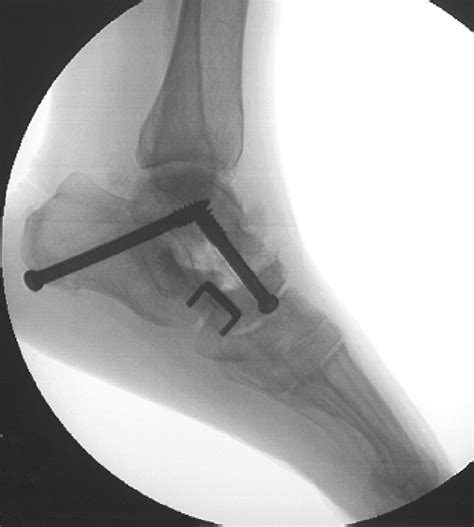

What to Expect During the Procedure

When you ask your surgeon, "What is arthrodesis from a technical perspective?", they will explain that the surgery involves removing the remaining cartilage from the joint surfaces. Once the raw bone is exposed, the surgeon uses internal hardware—such as metal plates, screws, rods, or pins—to hold the bones in the correct position. Sometimes, a bone graft (either from your own body, a donor, or a synthetic source) is placed between the bones to encourage them to grow together, a process known as osteointegration. Over several months, the body bridges the gap with new bone tissue, completing the fusion.